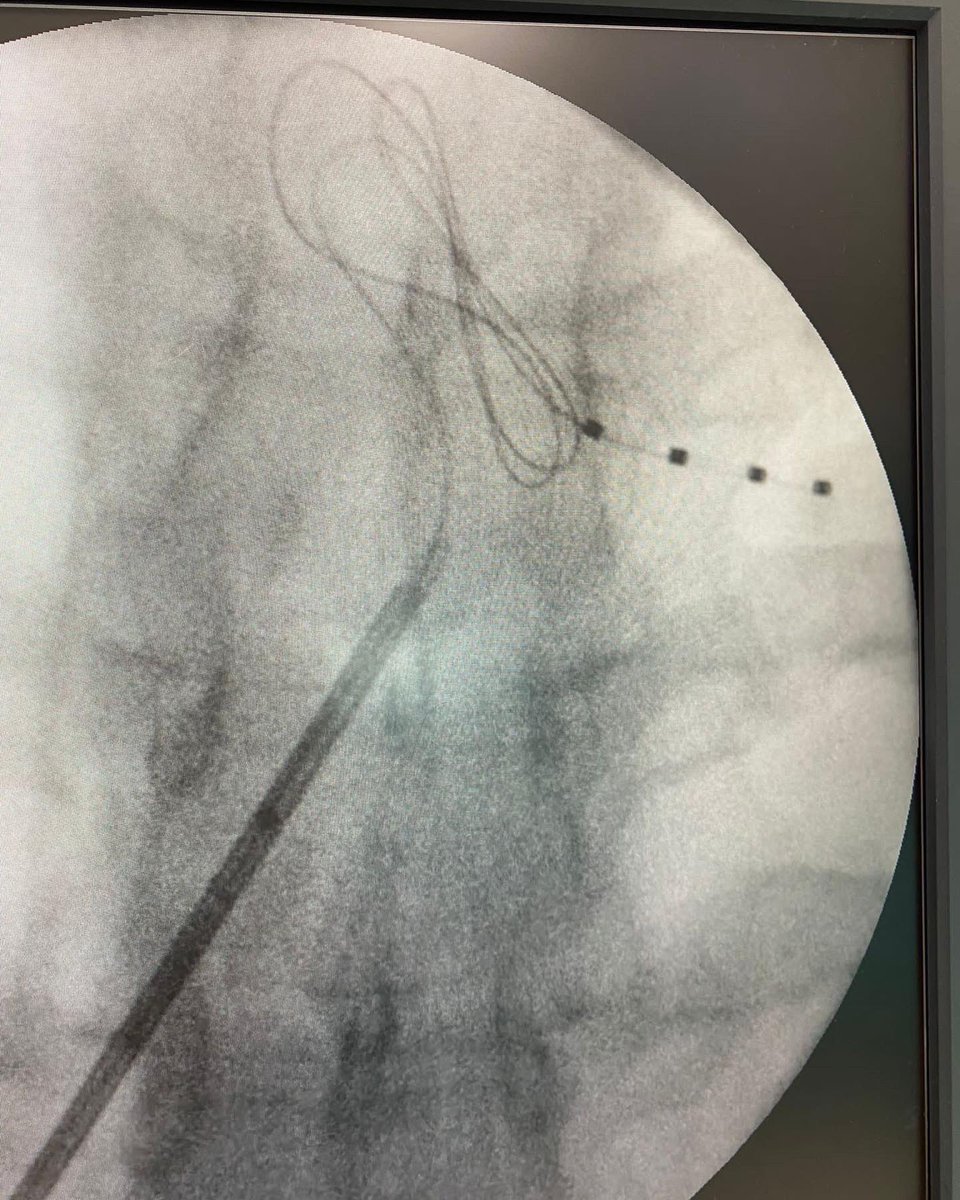

SDRC de rodilla. La importancia de una buena elección terapeutica hace que el alivio del dolor sea una realidad. Ayer implántanos elecyrodos de GRD en Pontevedra los Dres. Daniel Torres y Cristina Barreiro. Los servicios de anestesia: la piedra angular del tratamiento del dolor